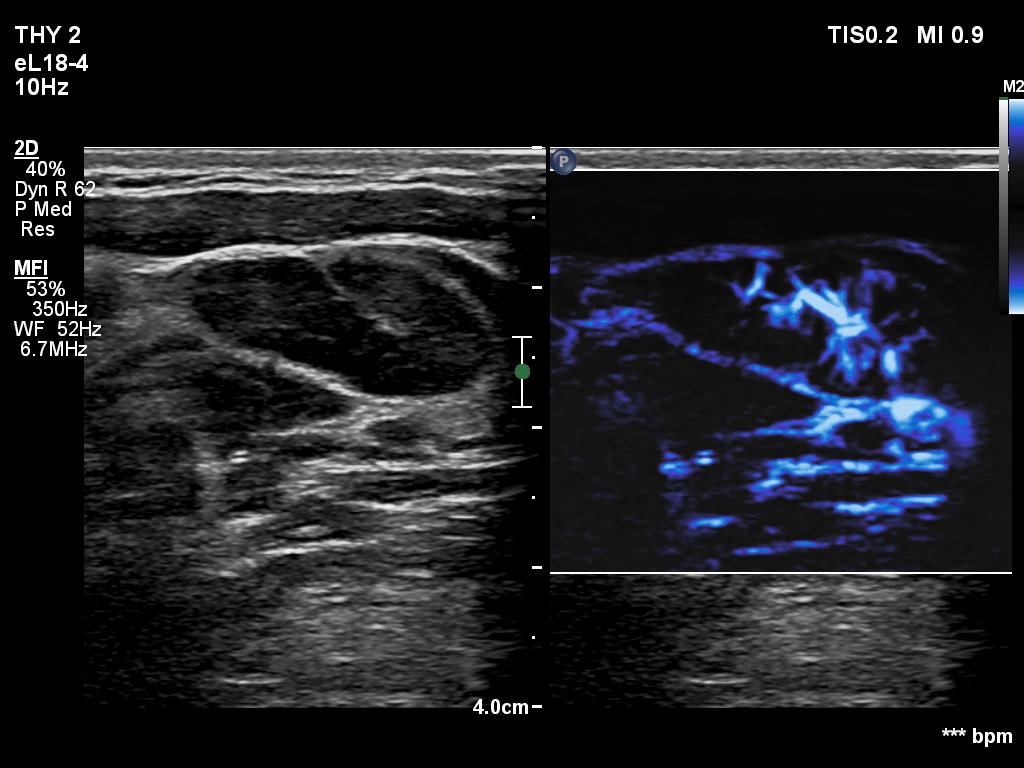

Right lobe, longitudinal scan

Lateral to the left lobe, longitudinal scan, microflow imaging. Note the irregular distribution of vessels.